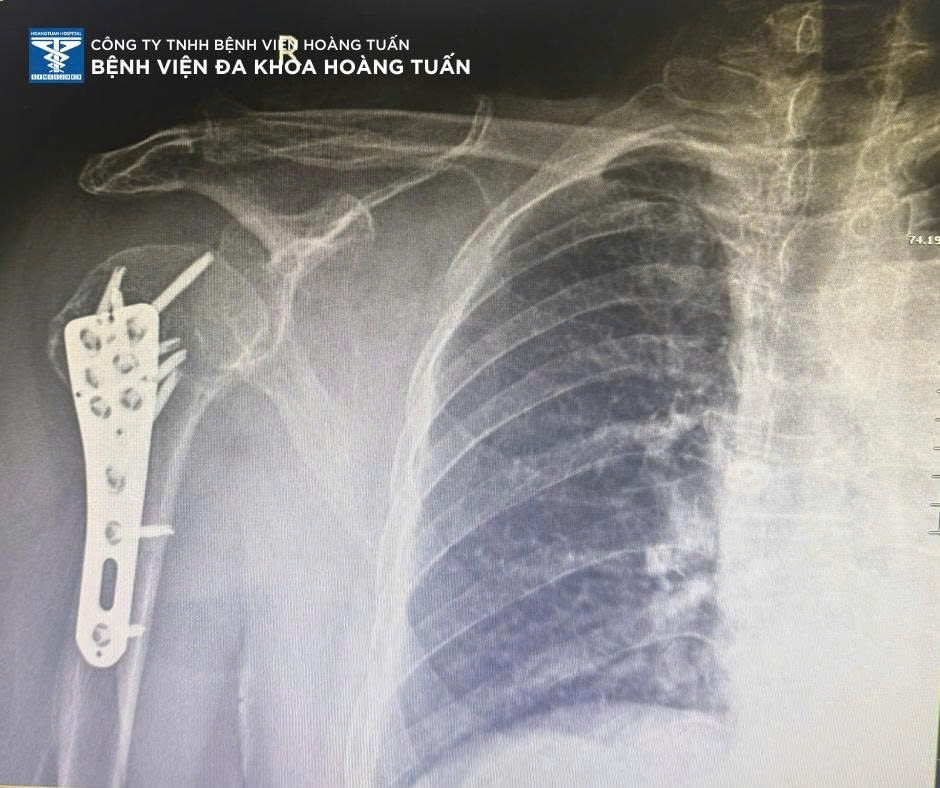

Qua thăm khám và chụp X-quang kiểm tra, BSCKI. Vũ Quốc Dũng – Khoa Ngoại CTCH Bệnh viện Đa khoa Hoàng Tuấn xác định bệnh nhân có tình trạng gãy đầu trên xương cánh tay phải kèm trật khớp vai phải, một tổn thương phức tạp, thường gặp ở người lớn tuổi do xương loãng, dễ gãy khi chấn thương.

Ekip phẫu thuật cùng các y bác sĩ tại Bệnh viện Đa khoa Hoàng Tuấn tiến hành phẫu thuật nắn trật khớp và kết hợp xương vai phải thành công. Sau phẫu thuật, tình trạng sức khỏe bệnh nhân ổn định, vận động vai đang được phục hồi tốt dưới sự hướng dẫn của đội ngũ vật lý trị liệu.